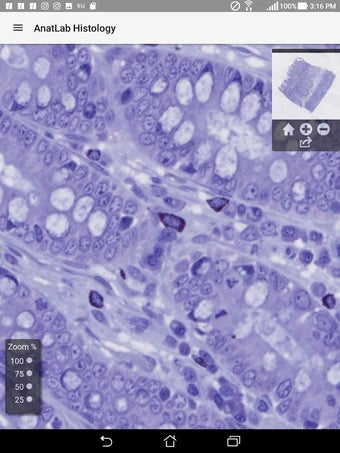

AnatLab Histología: Un atlas histológico completo.

AnatLab Histology es una aplicación gratuita para Android desarrollada por Eolas Technologies Inc. que proporciona a los usuarios imágenes de diapositivas microscópicas de ultra alta resolución. Esta aplicación es una herramienta ideal para estudiantes, profesores, investigadores y el público en general. Con esta aplicación, pueden explorar el paisaje microscópico completo del cuerpo como si estuvieran mirando una colección de diapositivas reales en un microscopio físico. Tiene una función basada en la nube, la aplicación se puede acceder en cualquier dispositivo móvil Android, lo que la hace muy conveniente y accesible.

La aplicación ofrece una colección completa de imágenes de diapositivas microscópicas de histología que se pueden ver en ultra alta resolución. Las imágenes son de calidad excepcional y proporcionan una representación precisa del paisaje microscópico del cuerpo. La aplicación es fácil de usar y navegar, lo que permite a los usuarios explorar diferentes partes del cuerpo con facilidad.